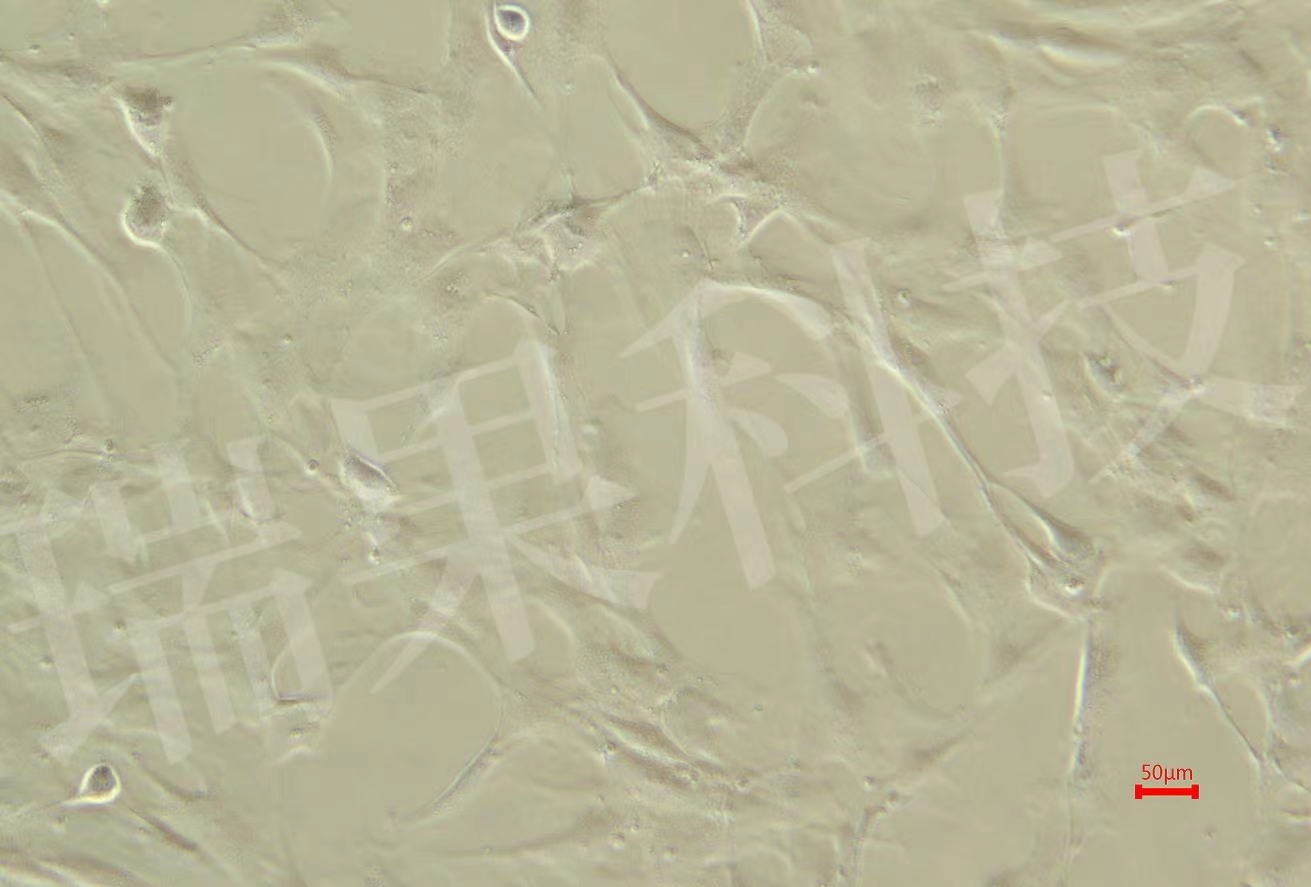

• 糖尿病肾病模型

提供系统的糖尿病肾病动物模型构建与表型分析服务,涵盖模型选...

糖尿病肾病模型

• 肿瘤模型

提供全面、专业的肿瘤动物模型构建与研究服务,覆盖从基础研究...

肿瘤模型